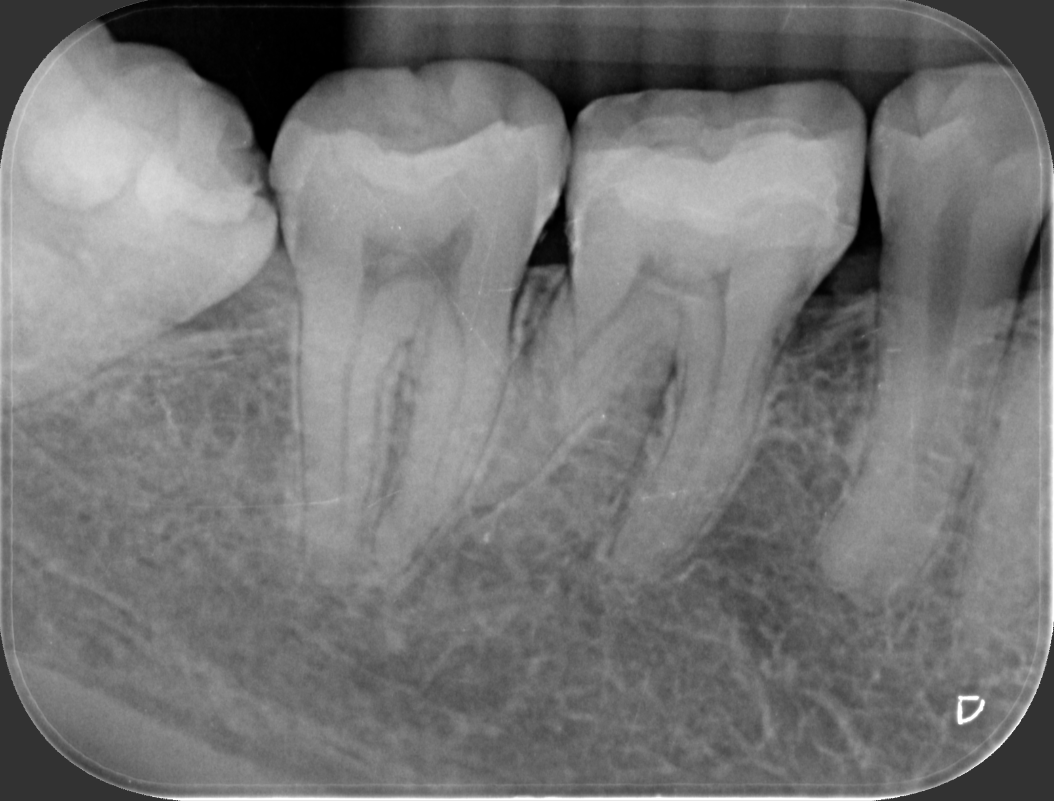

術後X光片